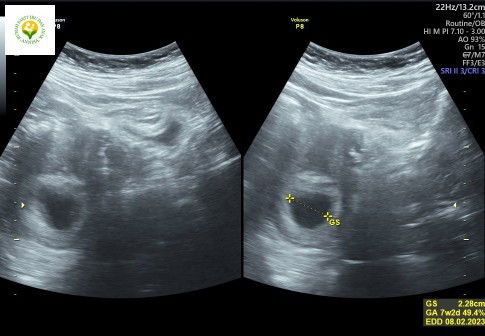

Usia Kantong & Bakal Janin berbeda, selisih beberapa hari apakah normal?

Jadi aku dikehamilan sebelumnya divonis BO. Nah aku alamin perbedaan usia kehamilan dengan usg yang cukup jauh sekitar 3 minggu dikehamilan pertamaku, janin dinyatakan tidak berkembang. Di kehamilan ke 2 aku ini juga mengalami perbedaan selisih waktu sekitar 2 harian dari perhitungan HPT aku, kata dokter ditunggu 1 bulan lagi, ada yang punya pengalaman sama?#MasyaAllahTabarakaAllah #seriusnanya #bantusharing